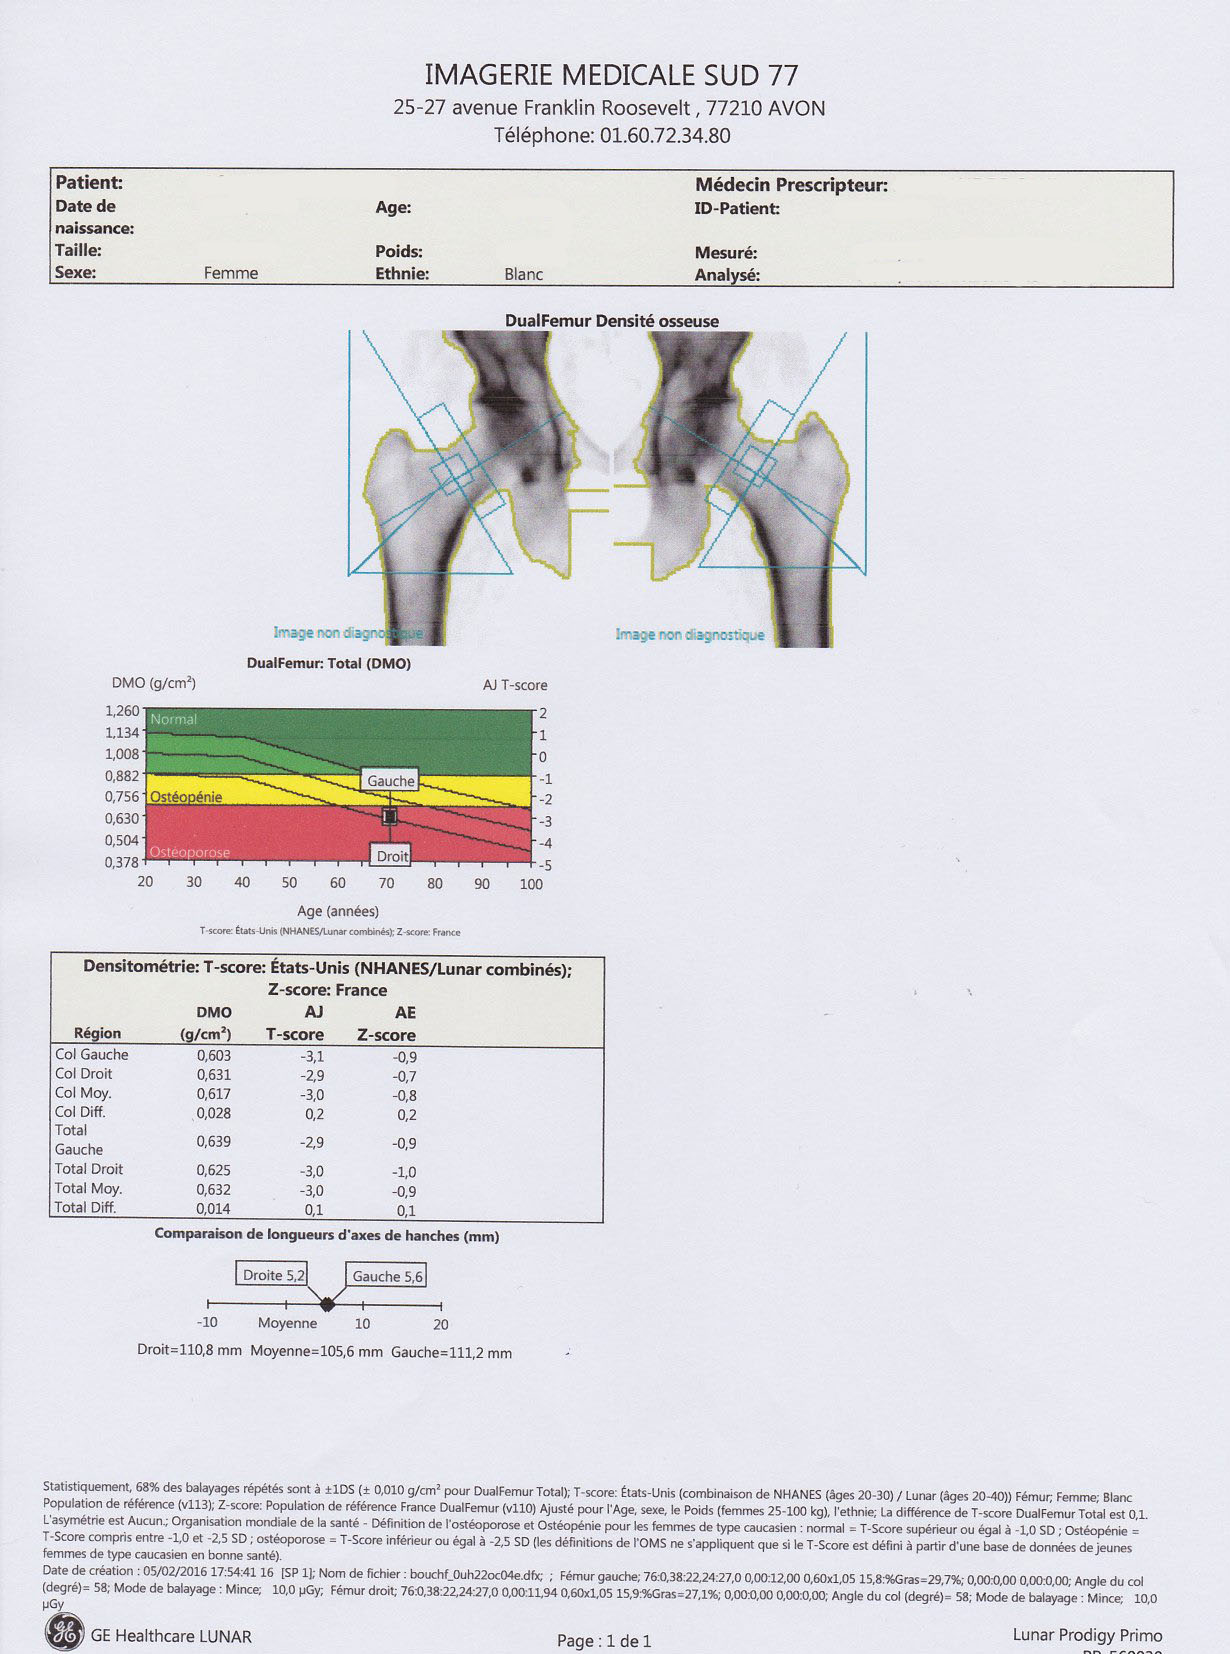

L'ostéodensitométrie biphotonique ou DXA est la technique de référence pour mesurer la déminéralisation appelée DMO par rapport au capital osseux initial. Elle permet aussi de surveiller un traitement de l'ostéoporose.

Des radiographies standards du rachis et des hanches sont réalisées avant l'ostéodensitométrie. Les mesures sont effectuées sur deux sites de référence: le rachis lombaire et le col fémoral ( éventuellement sur le poignet). Il se déroule selon les normes fixées par l'Afssaps et dans les conditions préconisées par l'HAS. L'absorption du faisceau par le squelette est analysée au cours de l'examen.

Résultats de la DMO

Le résultat mesure l'écart entre la valeur du patient et la valeur de référence mesurée chez l'adulte jeune au niveau de la même localisation osseuse. La valeur de référence correspond au pic de masse osseuse, capital osseux maximum atteint à la fin de la croissance.

Le Tscore correspond à la valeur de la densité minérale osseuse, la DMO mesurée en écart type par rapport à la valeur de référence représentée par la DMO moyenne d'un groupe de sujets jeunes( 20-30 ans) de même sexe.

La phase normale correspond à une densité normale: la DMO est supérieure à la moyenne de référence chez l'adulte jeune mois un écart type ( Tscore > -1)

L'ostéopénie correspond à une densité faible: la DMO est comprise entre la moyenne de référence chez l'adulte jeune moins un écart type et la moyenne de référence chez l'adulte jeune mois 2,5 écart type (-2,5 < Tscore <-1)

L'ostéoporose à une densité faible: la DMO est inférieure à la moyenne de référence chez l'adulte jeune moins 2,5 ecart type (Tscore < -2,5).